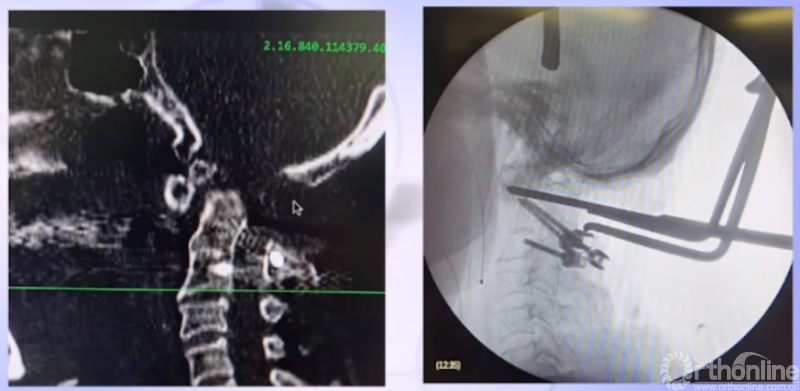

检查资料

CT

CTA

术后CT